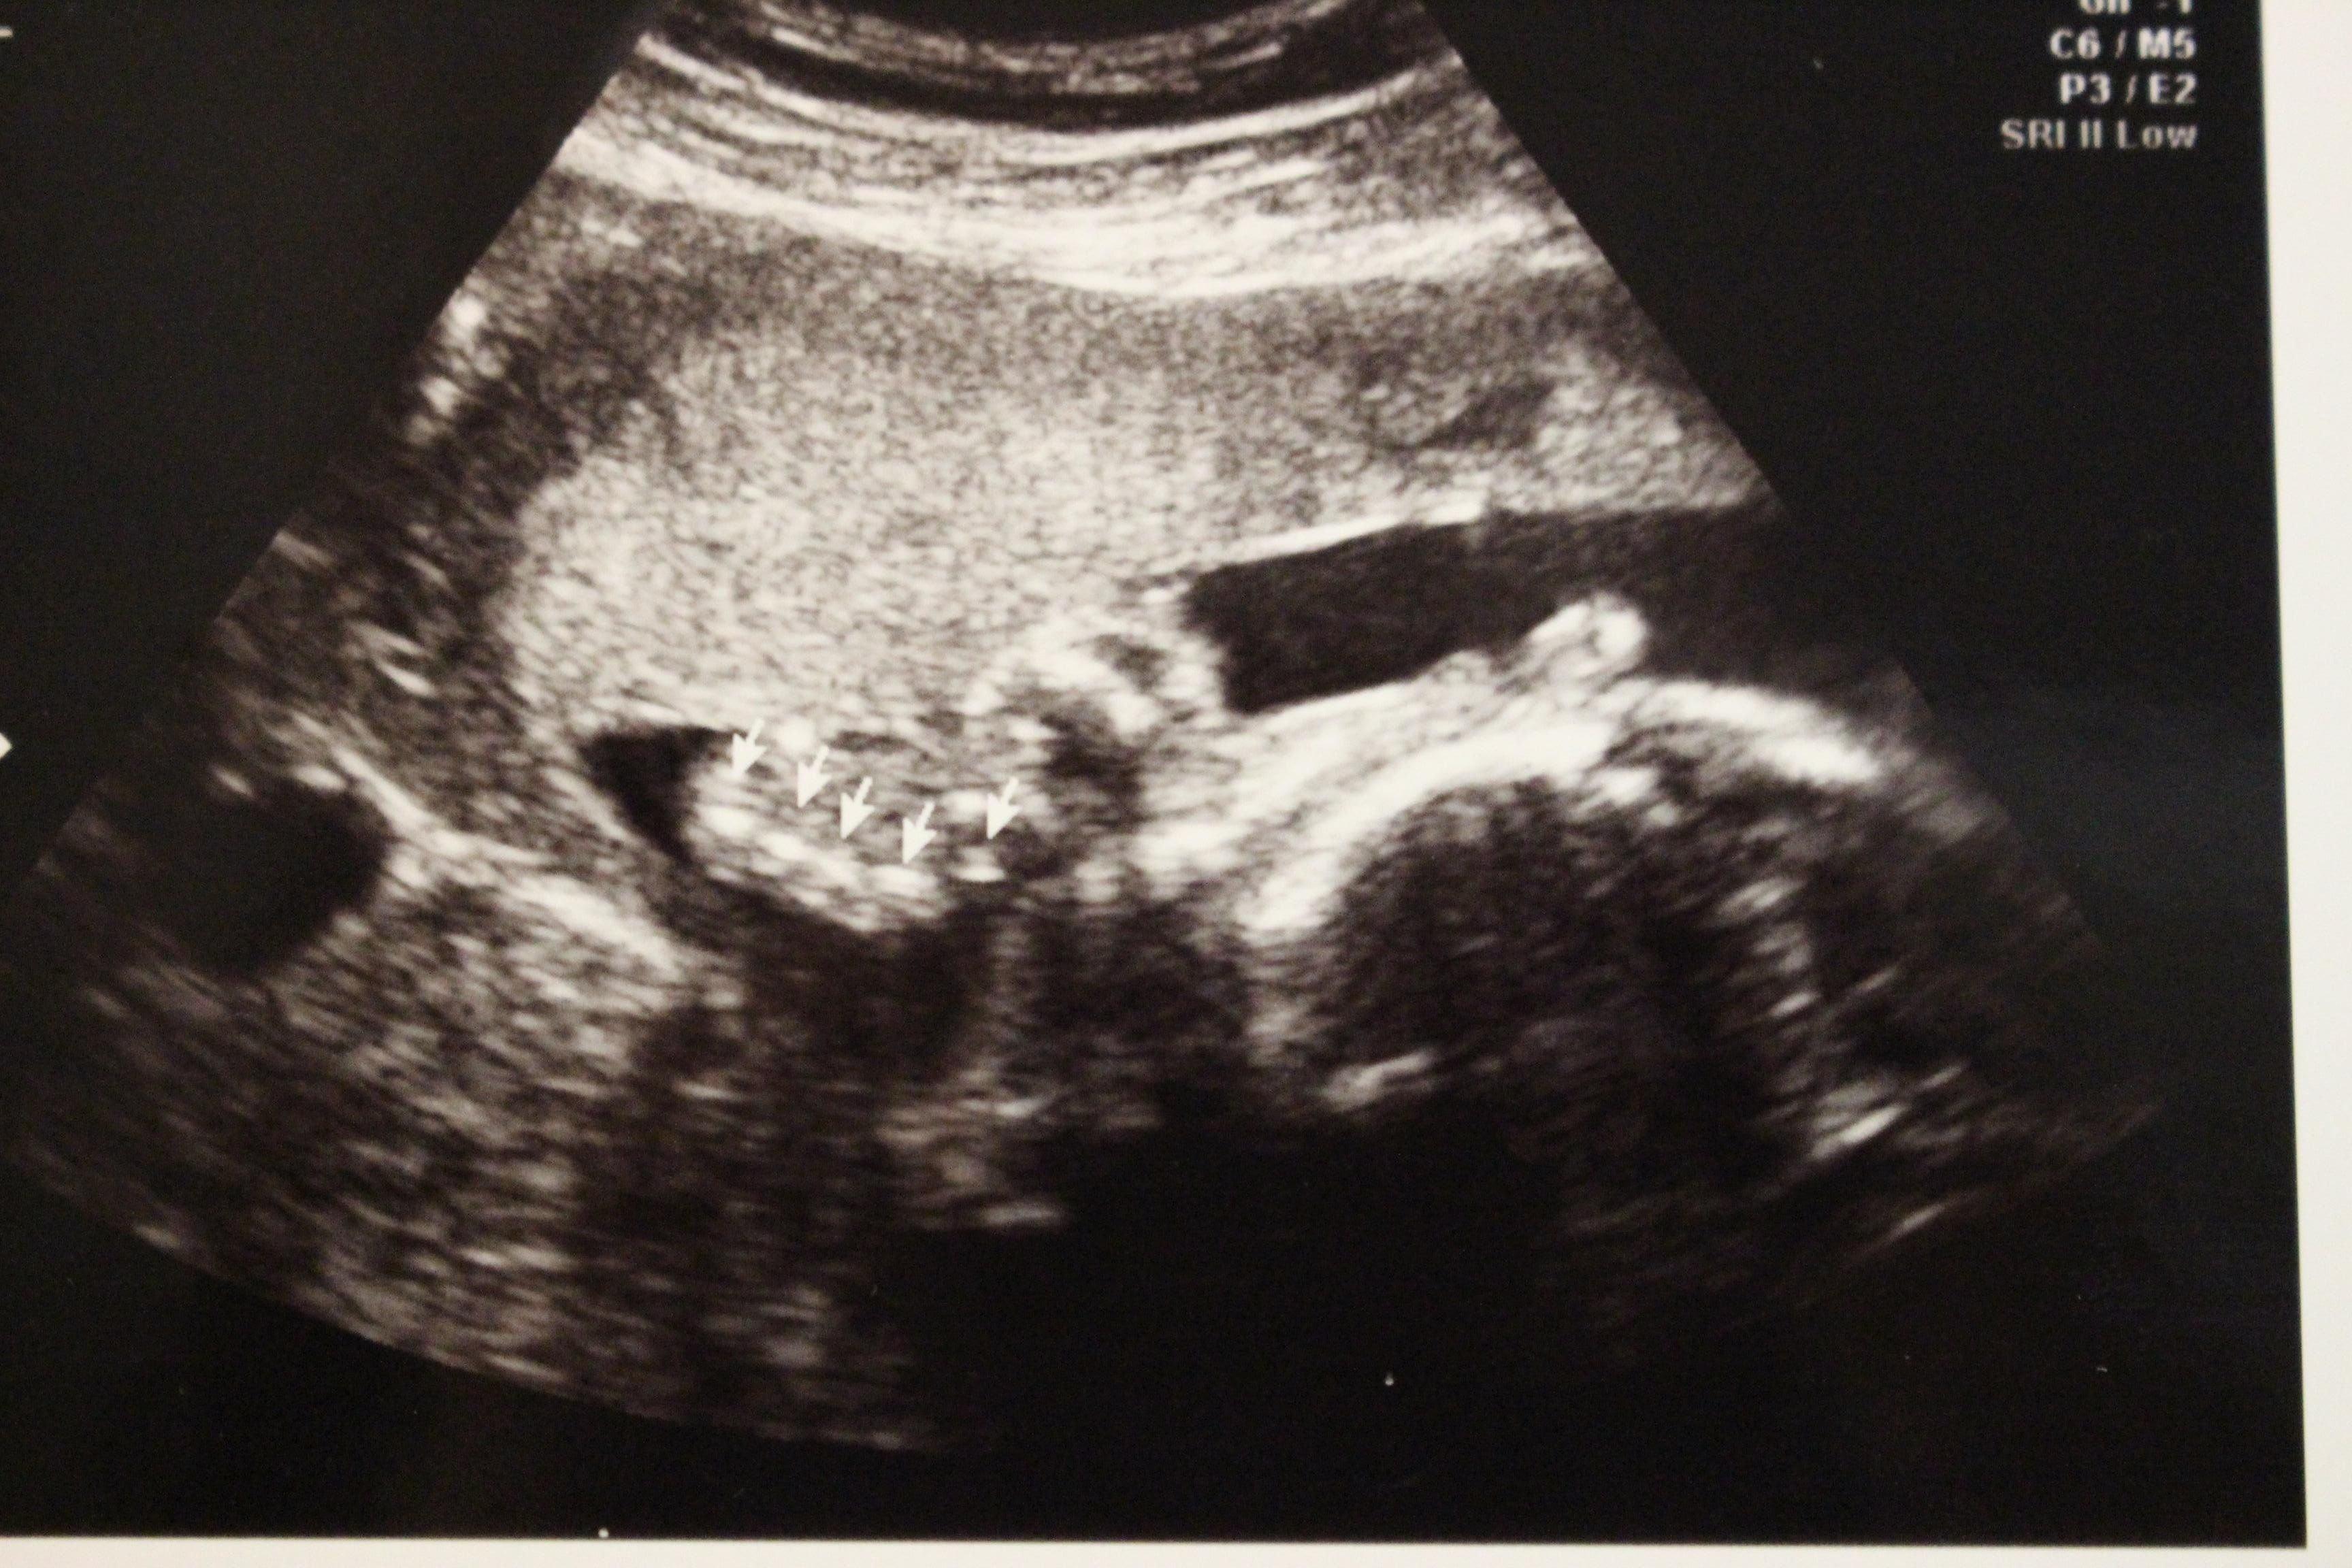

妊娠25週目のエコー写真

妊娠25週目、別の角度から撮った写真。手の指が5本あることを教えてもらいました。念のため受けた子宮頸管の長さを測る検査で「切迫早産」と診断を受け、そのまま人生初の車椅子に乗せられて、人生初の入院生活がスタートしたのでした。